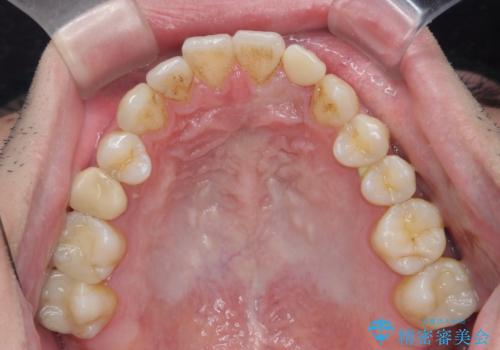

前歯の矮小歯 奥歯の反対咬合 をインビザラインで

- 上下の前歯が気になり来院。

左上2が矮小歯で小さく、また、左の奥歯が反対咬合になっていました。

左上2番はセラミッククラウンで反対側と同じ大きさにしました。

今回は下の前歯を1本抜くことで、下の奥歯をしっかり内側に傾けて治療を行いました。